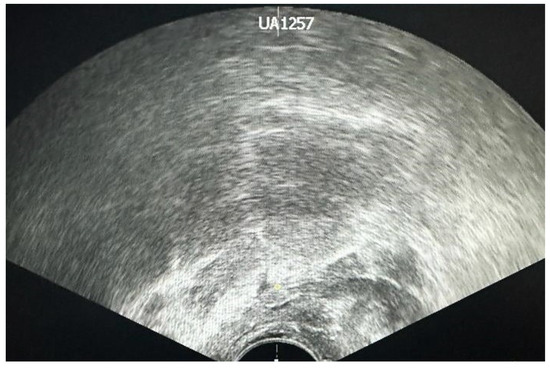

4. Transrectal Ultrasound (TRUS)-Guided Prostate Biopsy

6. Technical Difficulties

6.2. Prostatic Diameter and Volume

6.3. Benign Prostatic Hyperplasia (BPH)